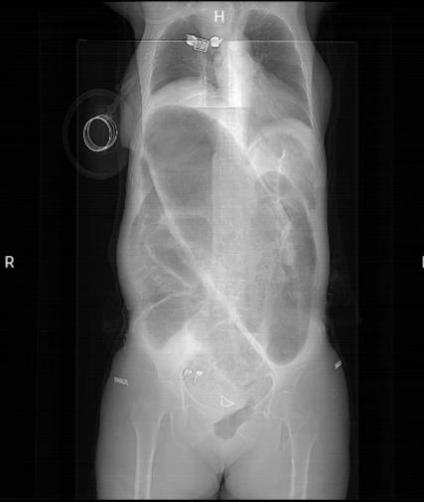

术前影像

入院后完善相关检查,经介入团队留置肠梗阻导管(经鼻型、经肛型),肠梗阻导管由硅橡胶制成,富于柔韧性,有效吸引肠道内容物,充分减轻肠道压力、肠道准备,为患者能够行全腹腔镜全结肠切除提供了重要的先决条件。我院普外三科邵学谦主任及其团队在手术室团队的协助下完成了全腹腔镜下全结肠切除术。术后患者病情恢复良好,便秘症状得到了完全缓解,生活质量得到了显著提高。